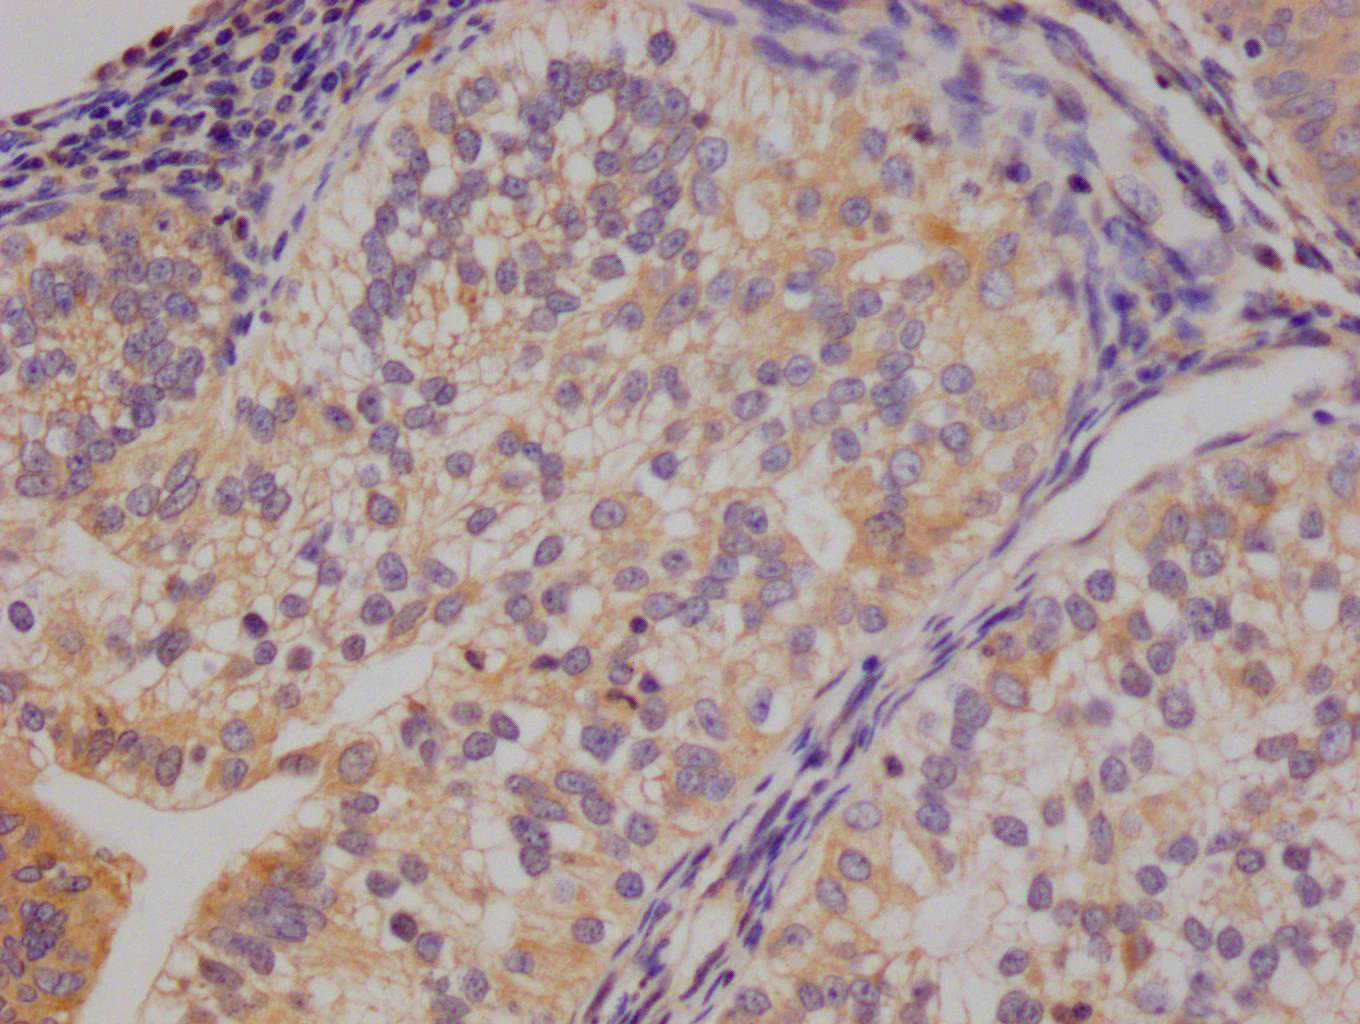

Gel: 8%SDS-PAGE, Lysate: 40 μg, Lane: Human esophagus cancer tissue, Primary antibody: CSB-PA297945(KRT13 Antibody) at dilution 1/500, Secondary antibody: Goat anti rabbit IgG at 1/8000 dilution, Exposure time: 40 seconds